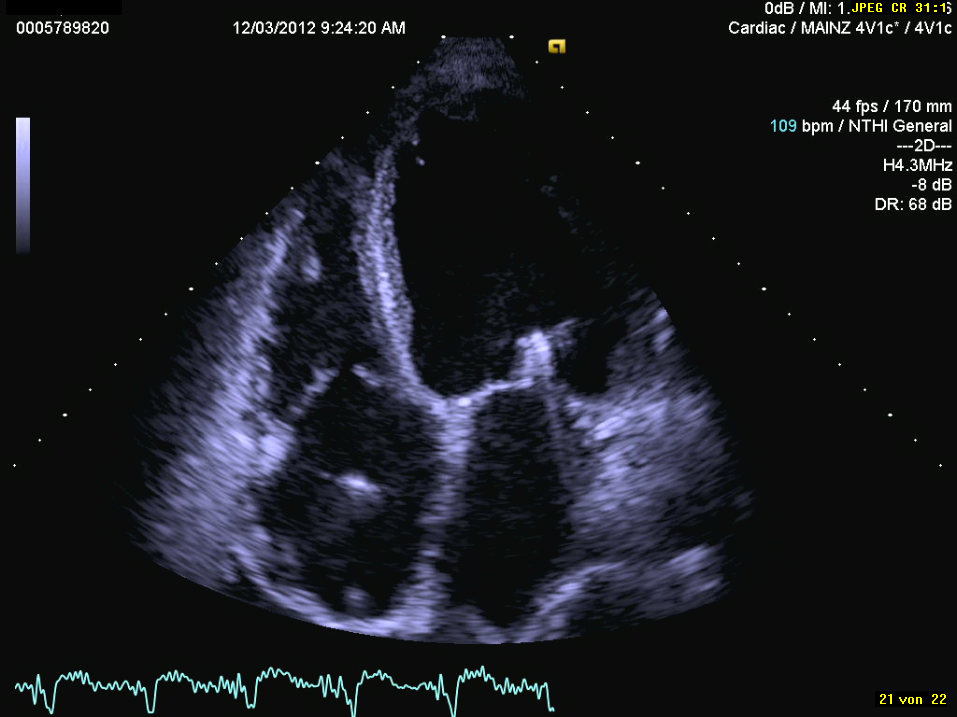

Die Herzultraschall-Untersuchung in Ruhe ist der Standard zur Beurteilung von Herzgröße, Pumpfunktion und Funktion der Herzklappen. Die Untersuchung wird bei freiem Oberkörper in Linksseitenlage durchgeführt. Dadurch liegt das Herz besser der Brustwand an und läßt sich besser untersuchen. Die Untersuchung ist in der Regel nicht schmerzhaft oder unangenehm. Die Untersuchung dauert etwas 10 Minuten und ist natürlich abhängig von der individuellen Schallbarkeit des Patienten. Man muß für die Untersuchung nicht nüchtern sein und erhält im Normalfall keine Medikamente, die Fahrtüchtigkeit beeinträchtigen.